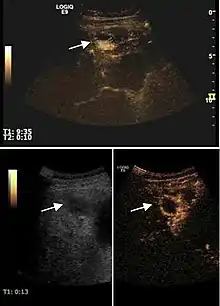

US examination is required to detect liver metastases in patients with oncologic history. In addition, the method can incidentally detect metastases in asymptomatic patients. Early identification (small sizes, small number) is important to establish an optimal course of treatment which can be complex (chemotherapy, radiofrequency ablation, surgical resection) but welcomed. In addition, discrimination of synchronous lesions that have a different nature is also important knowing that up to 25–50% of liver lesions less than 2 cm detected in cancer patients may be benign . US sensitivity for metastases detection varies depending on the examiner's experience and the equipment used and ranges between 40 and 80% . Sensitivity is conditioned by the size and acoustic impedance of the nodules. For a lesion diameter below 10 mm US accuracy is greatly reduced, reaching approx. 20%. Other elements contributing to lower US performance are: excessive obesity, fatty liver disease, hypomobility of the diaphragm, and certain patterns of hyperechoic or isoechoic metastases that can be overlooked or can mimic benign conditions. Conventional US appearance of metastases is uncharacteristic, consisting of circumscribed lesions, with clear, imprecise or "halo" delineation, with homogeneous or heterogeneous echo pattern. They can be single (often liver metastases from colonic neoplasm) or multiple. Echogenity is variable. When increased, they can compress the bile ducts (which may be dilated) and the liver vessels. Liver involvement can be segmental, lobar or generalized. In this situation a pronounced hepatomegaly occurs. Generally, metastases have non-characteristic Doppler vascular pattern, with few exceptions (carcinoid metastases). Cyst-adenocarcinoma metastases due to semifluid content may have a transonic appearance. When increasing, they can result in central necrosis. CEUS examination is a real breakthrough for detection and characterization of liver metastases.

Increased performance is based on identifying specific vascular patterns during the arterial phase and seeing metastases in contrast to normal liver parenchyma during the sinusoidal phase. CEUS increased accuracy is due to the different behavior of normal liver parenchyma (captures CA in Kuppfer cells) against tumor parenchyma (does not contain Kuppfer cells, therefore CEUS appearance is hypoechoic). To this adds the particularities of intratumoral circulation represented by a reduced arterial bed compared to that of the surrounding normal liver and the absence of the portal vessels . In terms of vascularity, metastases can be hypovascular (in gastric, colonic, pancreatic or ovarian adenocarcinomas) with hypoechoic pattern during arterial phase, and similar during portal venous and late phases, respectively hypervascular (neuroendocrine tumors, malignant melanoma, sarcomas, renal, breast or thyroid tumors) with hyperechoic appearance during arterial phase, with washout during the portal venous phase and hypoechoic pattern 30 seconds after injection.